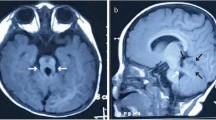

The patient was diagnosed as congenital glaucoma and underwent trabeculotomy twice at the age of 1 and 2-year-old, respectively. Combined with Latanoprost, Brinzolamide and Timolol Maleate eye drops, the intraocular pressure of both eyes have been normal since the surgery until 5 months ago, after going through the surgery of correction of lower eyelid inversion combined with ptosis. When admitted to the hospital, the patient can’t cooperate with visual acuity or other ocular examination. Examination of the eyes under general anesthesia showed a horizontal corneal diameter of 13 mm in the right eye and 15 mm in the left eye. Schiotz tonometry showed an intraocular pressure of 40.08 mm Hg in the right eye and 14.57 mm Hg in the left eye. The axial lengths were 29.7 mm in the right eye and 30.8 mm in the left eye. In his right eye, ectopia lentis was noted, and he had a cataract in the lens, corneal clouding, iris coloboma, and no light reflex. In the left eye, he had relatively clear cornea, iris atrophy with peripheral incision in the superior, pale optic disc and choroidal atrophy (Fig. 2). The patient underwent vitrectomy, lens cutting, and internal transscleral ciliary body photocoagulation in his right eye. The intraocular pressure of the child was maintained at a normal level after the surgery.

In his right eye, ectopia lentis was noted, and he had a cataract in the lens, corneal clouding, iris coloboma, and no light reflex (A). Fundus photography showed optic disc pale and choroidal atrophy in the right eye (B). In the left eye, he had relatively clear cornea, iris atrophy with peripheral incision in the superior (C), pale optic disc and choroidal atrophy (D)